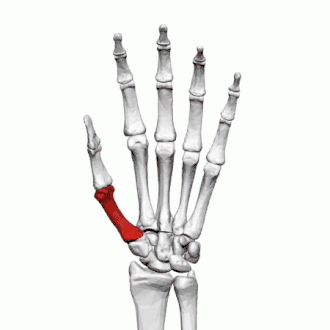

Premier métacarpien

Description

Le premier os métacarpien est le plus court et le plus épais des métacarpiens. Il est situé sur un plan plus antérieur et plus oblique.

Base

La surface articulaire de la base est en selle et s'articule avec le trapèze. La surface articulaire est délimitée par une crête épaisse en forme de crête s'étendant autour de sa circonférence.

Sur le côté palmaire et latéral de la base se trouve l'insertion du tendon du muscle long abducteur du pouce, généralement doté d'un petit tubercule.

La configuration de l'articulation carpo-métacarpienne du pouce joue un rôle important dans le mécanisme d'opposition.

Contrairement aux autres métacarpiens, le premier métacarpien n'a pas de facettes articulaires sur les côtés de sa base car il s'articule exclusivement avec le trapèze.